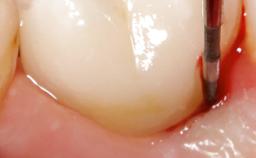

In this case, Nicola Zitzmann describes the sudden loss of a previously well-osseointegrated implant that had been in healthy function for 5 years. The case includes recommendations for occlusion and function of implant restorations. A 74-year-old patient had received implant-fixed dental prostheses in the maxilla in 2008, and in the right mandible three years later. His tooth loss was mainly related to recurrent caries associated with hyposalivation as a potential side effect of his cholesterol-lowering medication.